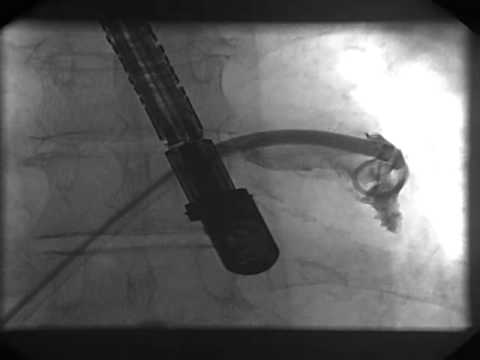

Video 16.8

Video 16.8 Wiring of the left upper pulmonary vein and introduction of the pigtail catheter.

Video 16.9

Video 16.9 Wiring of the left upper pulmonary vein and introduction of the pigtail catheter.